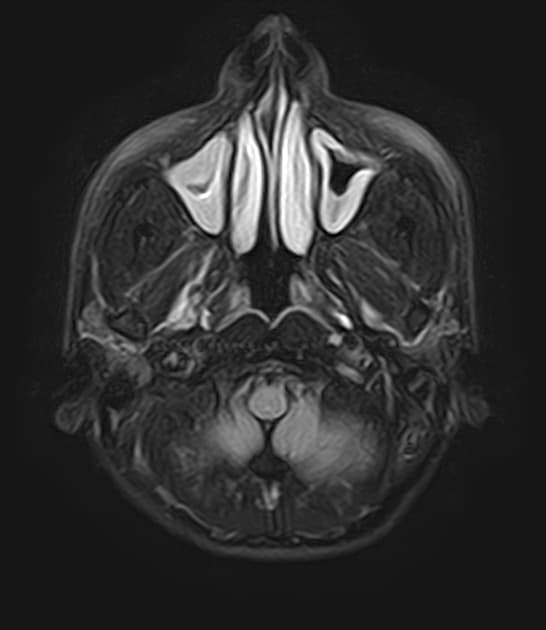

Vô kinh nguyên phát và giao hợp đau (dyspareunia).

- Không thấy tử cung và không có âm đạo rõ rệt.

- Buồng trứng hai bên được quan sát thấy.

Bệnh nhân có phần phụ bình thường và không có dị tật thận kèm theo nào khác, ngoại trừ hệ bài tiết kép bên trái.

Do đó, bệnh nhân này được xem là mắc dạng điển hình (type A) của hội chứng này, đặc trưng bởi sự vắng mặt bẩm sinh của tử cung và phần trên âm đạo, trong khi buồng trứng và vòi trứng vẫn bình thường.

Hội chứng Mayer-Rokitansky-Küster-Hauser (MRKH) là một dị tật bẩm sinh gặp ở khoảng 1 trên 4.500 trẻ nữ, do sự không phát triển của ống Müller trong quá trình phôi thai. Hội chứng được chia thành hai loại: loại A (dạng điển hình) với tình trạng không phát triển tử cung và phần trên âm đạo nhưng buồng trứng bình thường, và loại B (dạng không điển hình) kèm theo các dị tật ở các hệ khác. Chẩn đoán thường được xác định ở tuổi thiếu niên do vô kinh nguyên phát dù dậy thì diễn ra bình thường. Các phương tiện hình ảnh như siêu âm vùng chậu và cộng hưởng từ (MRI) rất quan trọng để xác nhận sự vắng mặt của tử cung và phần trên âm đạo, đồng thời phát hiện mô buồng trứng bình thường. Cần đánh giá các dị tật đi kèm, đặc biệt ở hệ tiết niệu (ví dụ: thận móng ngựa, không phát triển một bên thận) và hệ xương. Điều trị bao gồm hỗ trợ tâm lý, tạo âm đạo nhân tạo bằng phương pháp phẫu thuật hoặc không phẫu thuật, và tư vấn sinh sản, vì không thể mang thai tự nhiên, tuy nhiên có thể mang thai nhờ người mang thai hộ.